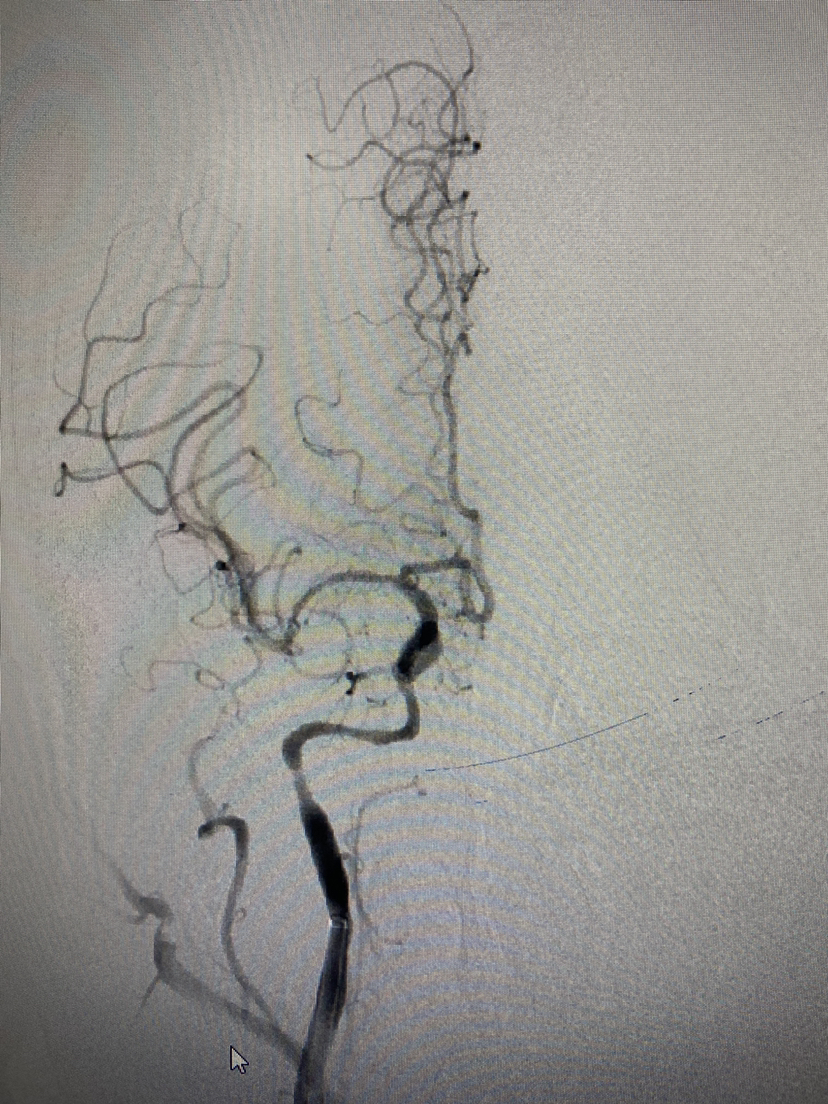

术前造影右侧大脑中闭塞